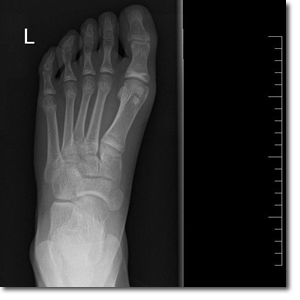

Paciente de 11 años que acude a Urgencias por dolor en el pie izquierdo de 6 meses de evolución, junto con inflamación de este en las últimas 24 horas. No guarda relación con traumatismo ni con sobreesfuerzo físico. A la exploración física, presenta dolor a la palpación en la articulación metatarsofalángica del primer dedo, con movilidad conservada. Se realiza radiografía de la extremidad (Figura 1 y Figura 2).